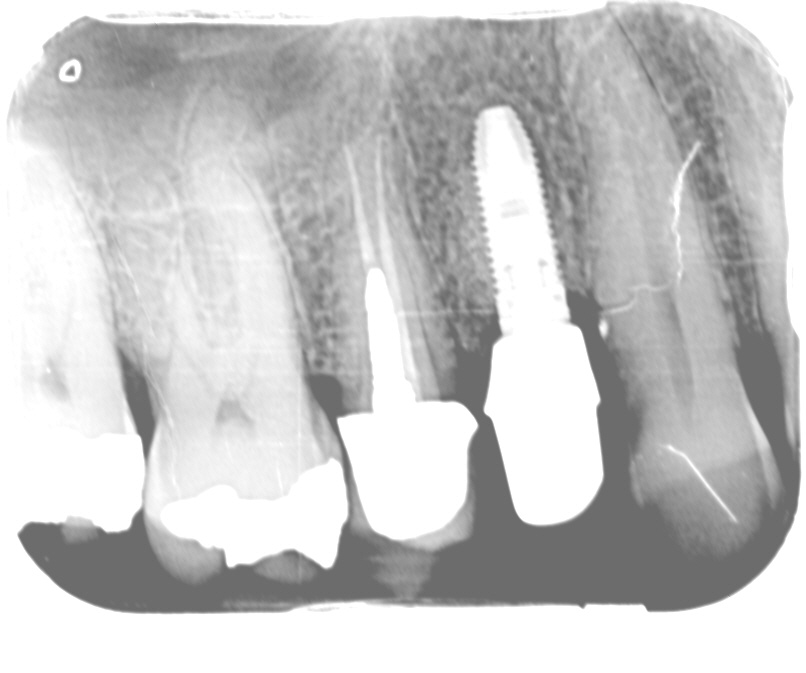

Hier is dan de foto die direct na plaatsing van het abutment/kroon door de tandarts gemaakt is (op 6-10-2010). Ruim een maand later (9-11-2010) kwam de opbouw/kroon los te zitten, d.w.z. kon die een beetje heen en weer bewogen worden. Dit gebeurde van het ene moment op het andere, terwijl ik (voorzichtig) zat te "poeren" met een tandenstokertje. De volgende dag ben ik door mijn tandarts gezien, die (vanwege zijn beperkte beschikbaarheid) een afspraak maakte - om de opbouw/kroon te verwijderen - voor 1-12, d.w.z. pas drie weken later! Omdat ik nogal last kreeg van het tandvlees dat ging ontsteken en ik gelezen had dat zo'n ruimte tussen opbouw en implantaat een reservoir vormt voor bacteriën, heb ik opde kaakchirurg geconsulteerd (zie foto van 12-11) en een implantoloog gezocht, voor een 2nd opinion en voor het verwijderen van de opbouw/kroon (op 15-11 gebeurd).

JW Vaartjes

Denk nog steeds niet echt dat torquewaarde hier een rol speelt.

Zoals vanaf het begin van de casus aangegeven, heb ik gesteld dat het bredere abutment zou stuiten tegen de botpiek links op de foto.

En inderdaad op deze x-foto lijkt dat nu te gebeuren... Er zit een kleine spleet tussen het abutment en het implantaat en het abutment staat in nauwe relatie met het approximale bot.

Het abutment botst dus op het bot, maar de torquewaarde wordt wel zonder problemen bereikt. Als echter dat bot resorbeert dan zit het abutment los en is deze casus gestart.

Inmiddels zal het abutment niet meer stuiten op het bot en kan de kroon opnieuw vastgezet worden/ zijn. Eind goed al goed.

Er is inderdaad na de afdruk en deze foto al bot verdwenen daar, maar als je goed kijkt zie je opaciteiten zeer dichtbij het abutment.

Je moet je voorstellen dat bot altijd bekleed is met botvlies en bindweefsel en afhankelijk waar je kijkt ook met epitheel. Deze laag de 'biological width' is voor botvlies en bindweefsel zeker 0,8mm dik en vaak dikker.

Op de röntgenfoto zou je kunnen zeggen dat er nog 'lucht' tussenzit maar in werkelijkheid is dus al het tandvlees dus samengeperst tot bijna niks en daardoor komt het abutment niet goed op zijn plek.